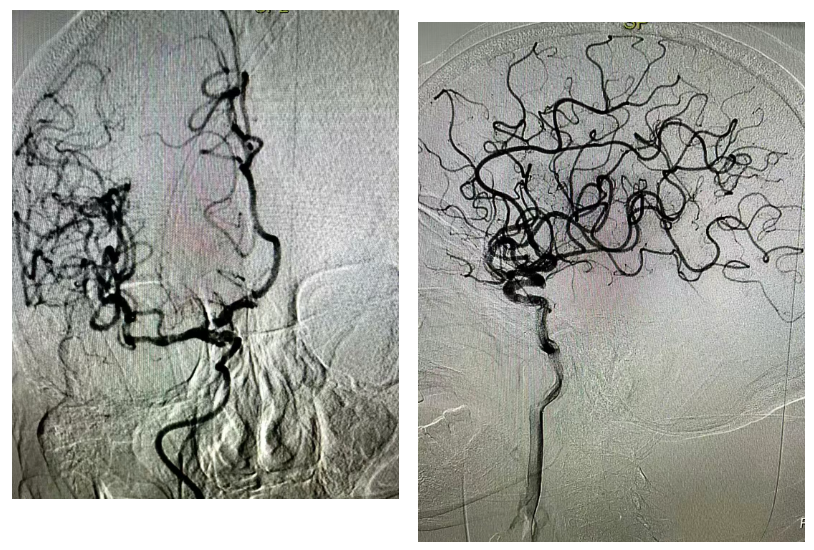

经股动脉穿刺置鞘,造影管依次行主动脉弓、双侧颈动脉、椎动脉造影——术中明确了“罪魁祸首”:右侧颈内动脉颅内段闭塞、右侧大脑中动脉闭塞。这两处关键血管的堵塞,正是导致老人意识障碍、肢体瘫痪的主要原因。

取栓过程同样步步惊心。手术团队操控超滑导丝,将长鞘精准送至右侧颈内动脉C1段,再引导微导管、微导丝穿过闭塞段,抵达右侧大脑中动脉M2段。确认位置无误后,取栓支架精准释放,牢牢嵌合血栓。

负压抽吸、回收支架——当支架取出的瞬间,一段约10mm的血栓被成功带出!

13:40,首次复查造影显示,右侧大脑中动脉血流完全再通;10分钟后再次复查,远端血管显影良好,脑实质、静脉期均无异常。13:50,顺利完成了这场高难度的高龄取栓攻坚战。